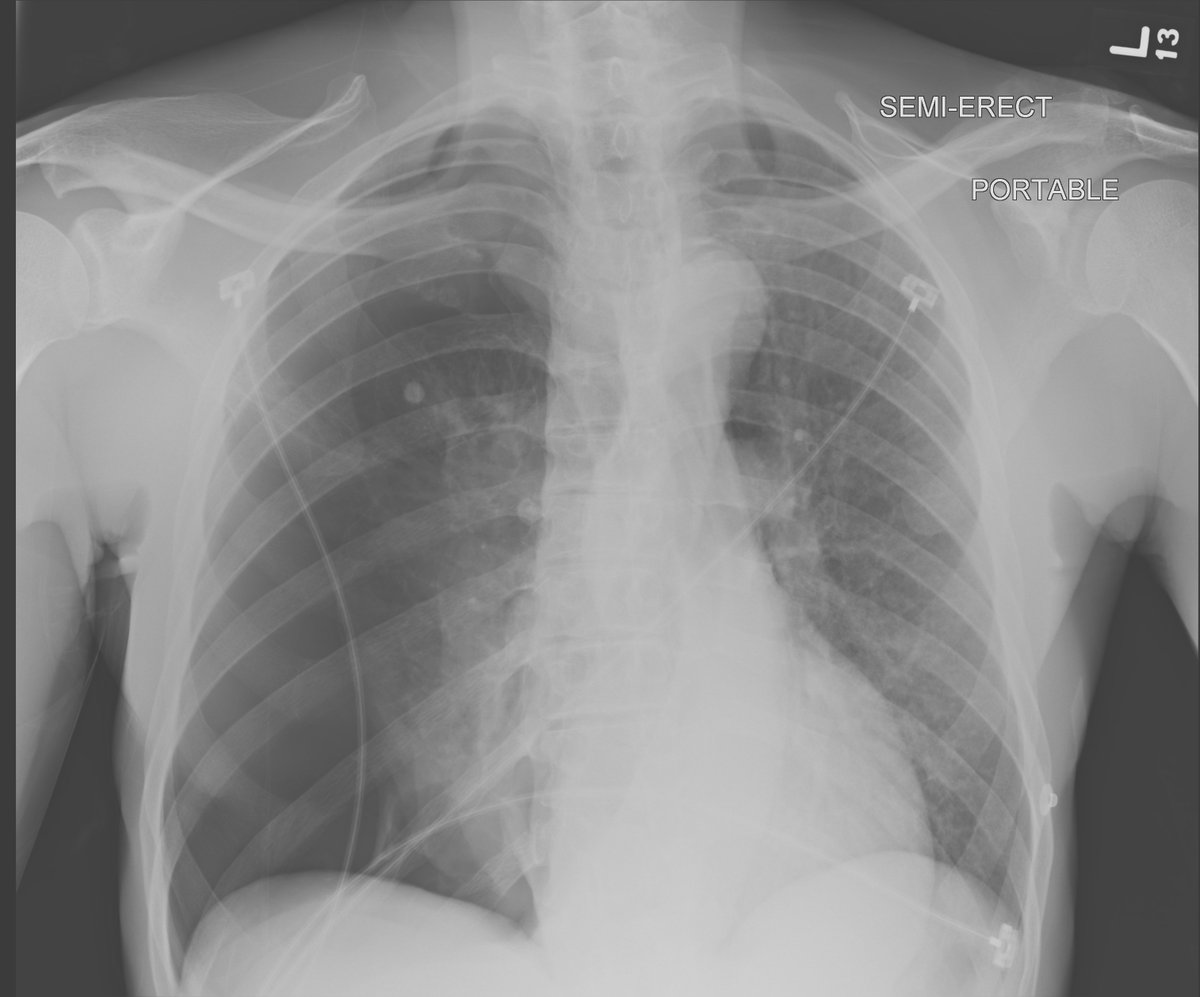

Re-expansion pulm. edema: rare important cause unilateral edema after (wait for it) rapid lung expansion after thoracentesis or PTX. Mortality up to 20%, prevent by removing < 1.5 L fluid. Complete recovery after < 1 week in this case. #chestraded #FOAMrad #FOAMed